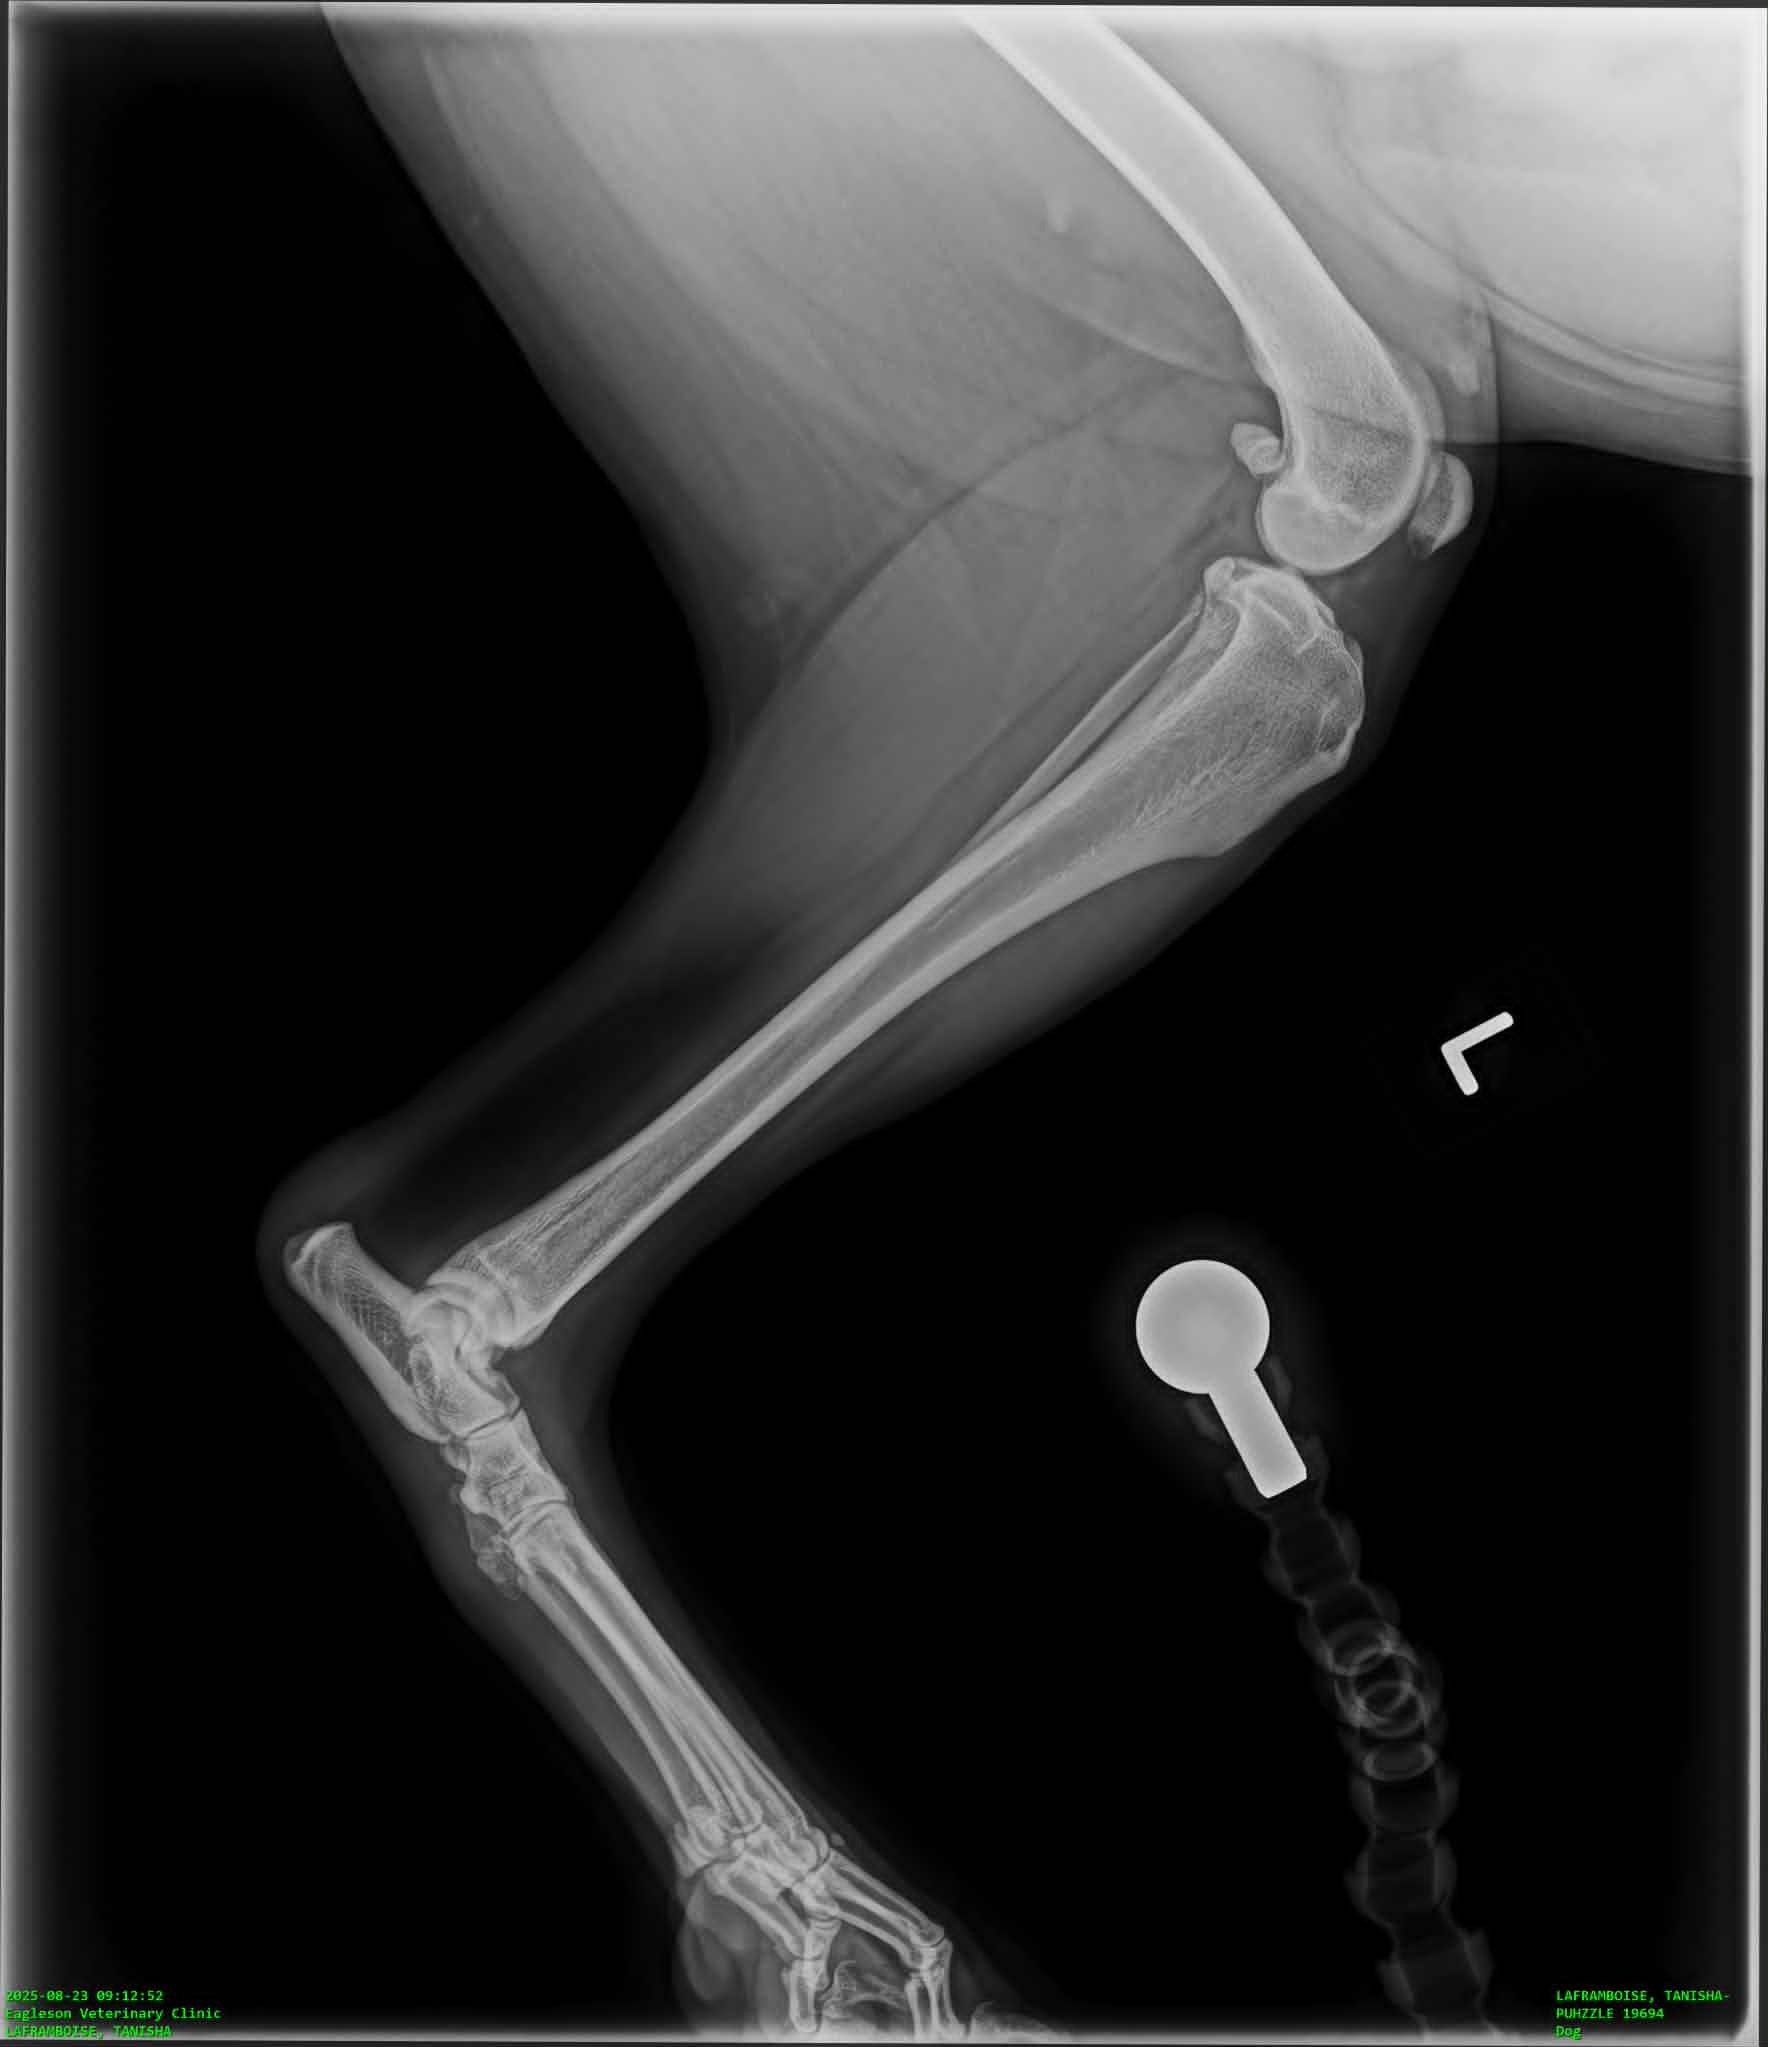

Hello my name is Zach and my wife Tanisha and I are desperately trying anything we can to raise the funds for our dog-ters TPLO surgery. After we had arrived home in the evening my wife noticed she was limping on her walk. We crate rested her for the night and woke up early to see if she would still be limping in the morning. When she was we immediately took her to emergency at our regular vet who did x-rays and actually diagnosed Puhzzle with Bi-lateral hip dysplasia and told us she would need hip surgery. We started some pain management and got a referal to an Orthopedic vet near us to start discussing options. During our consultation with our surgeon he mentioned feeling a little concerned about one of her x-rays and the consultation quickly turned into an exam. He explained to us that yes Puhzzle has Bi-lateral hip dysplasia, but as she's 4 and has had no issues running, jumping, or being a dog that he suspected her hips aren't her current issue. He did an exam on her legs and found she has a partially torn ACL that will require surgery to fix, luckily he mentioned that once they get the TPLO surgery they do not need another on that particular knee and she'll gain 98-99% functionality but the other ACL is high risk for injury within 6-12 months because this injury is genetic, being a structural flaw of how her liagaments rub on the bone while moving. My wife and I are saving everything we can and have her surgery currently scheduled for November 20th, because she needs the surgery sooner than later, to avoid further injuring herself, and any donation towards her surgery would mean so much to us.